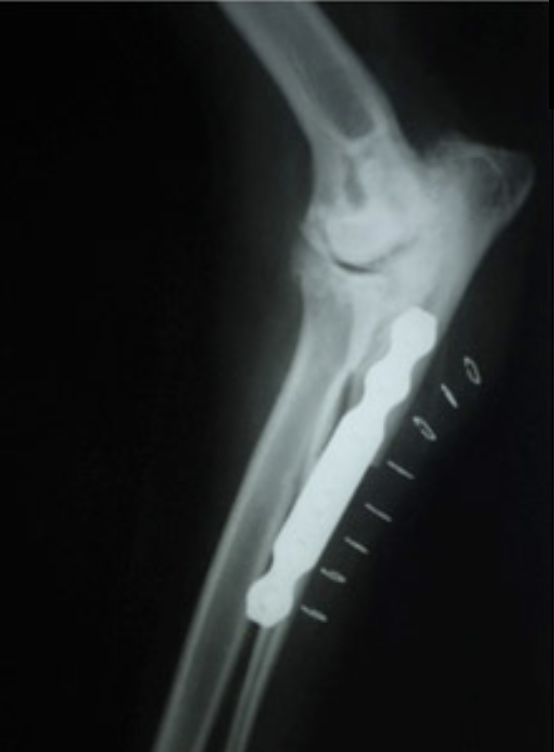

• Resolución de fracturas: técnicas MIPO en fracturas (guiadas con "Arco C")

• Endoprótesis y exoprótesis, en cirugías de salvamento de miembro